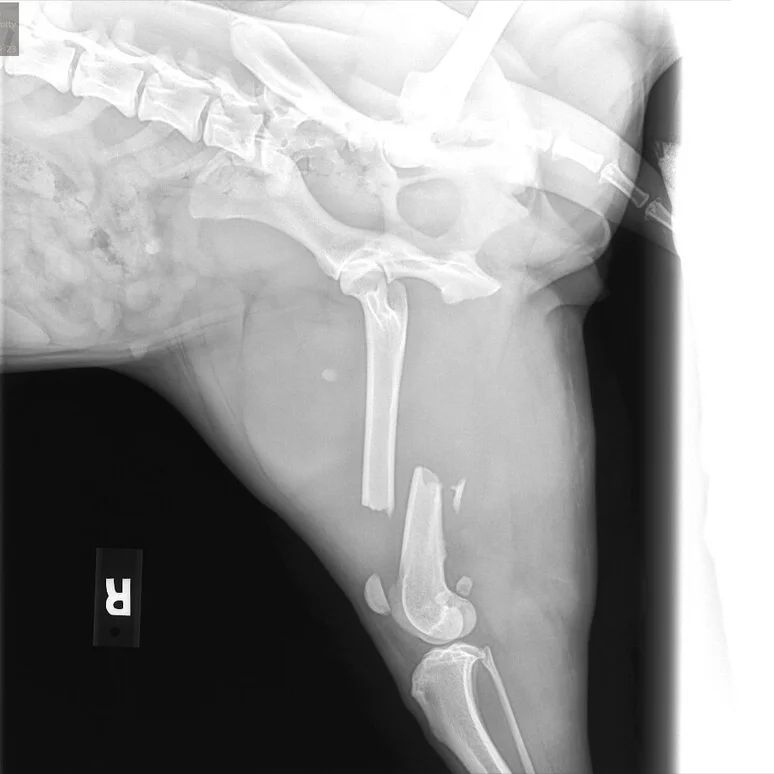

Honey Bunches’ situation was heartbreaking. She had been hit by an electric scooter, leaving her with a fractured femur. Surgery was essential, but neither her family nor the shelter had the means to cover the cost.

Honey Bunches underwent surgery soon after, and the results were remarkable.